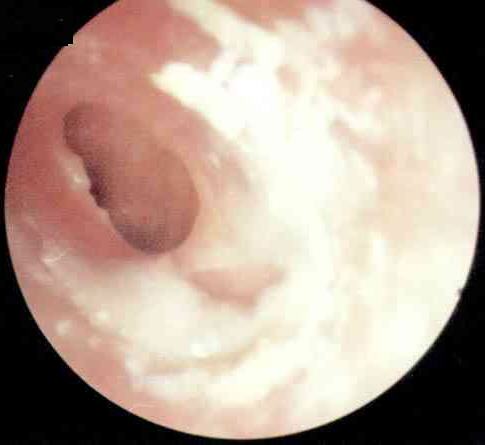

分泌性中耳炎的症状

分泌性中耳炎是以中耳积液及听力下降为特征的中耳非化脓性炎性疾病,又称为渗出性中耳炎、非化脓性中耳炎、黏液性中耳炎、卡他性中耳炎、鼓室积液、浆液性中耳炎、浆液—黏液性中耳炎、无菌性...[详细]